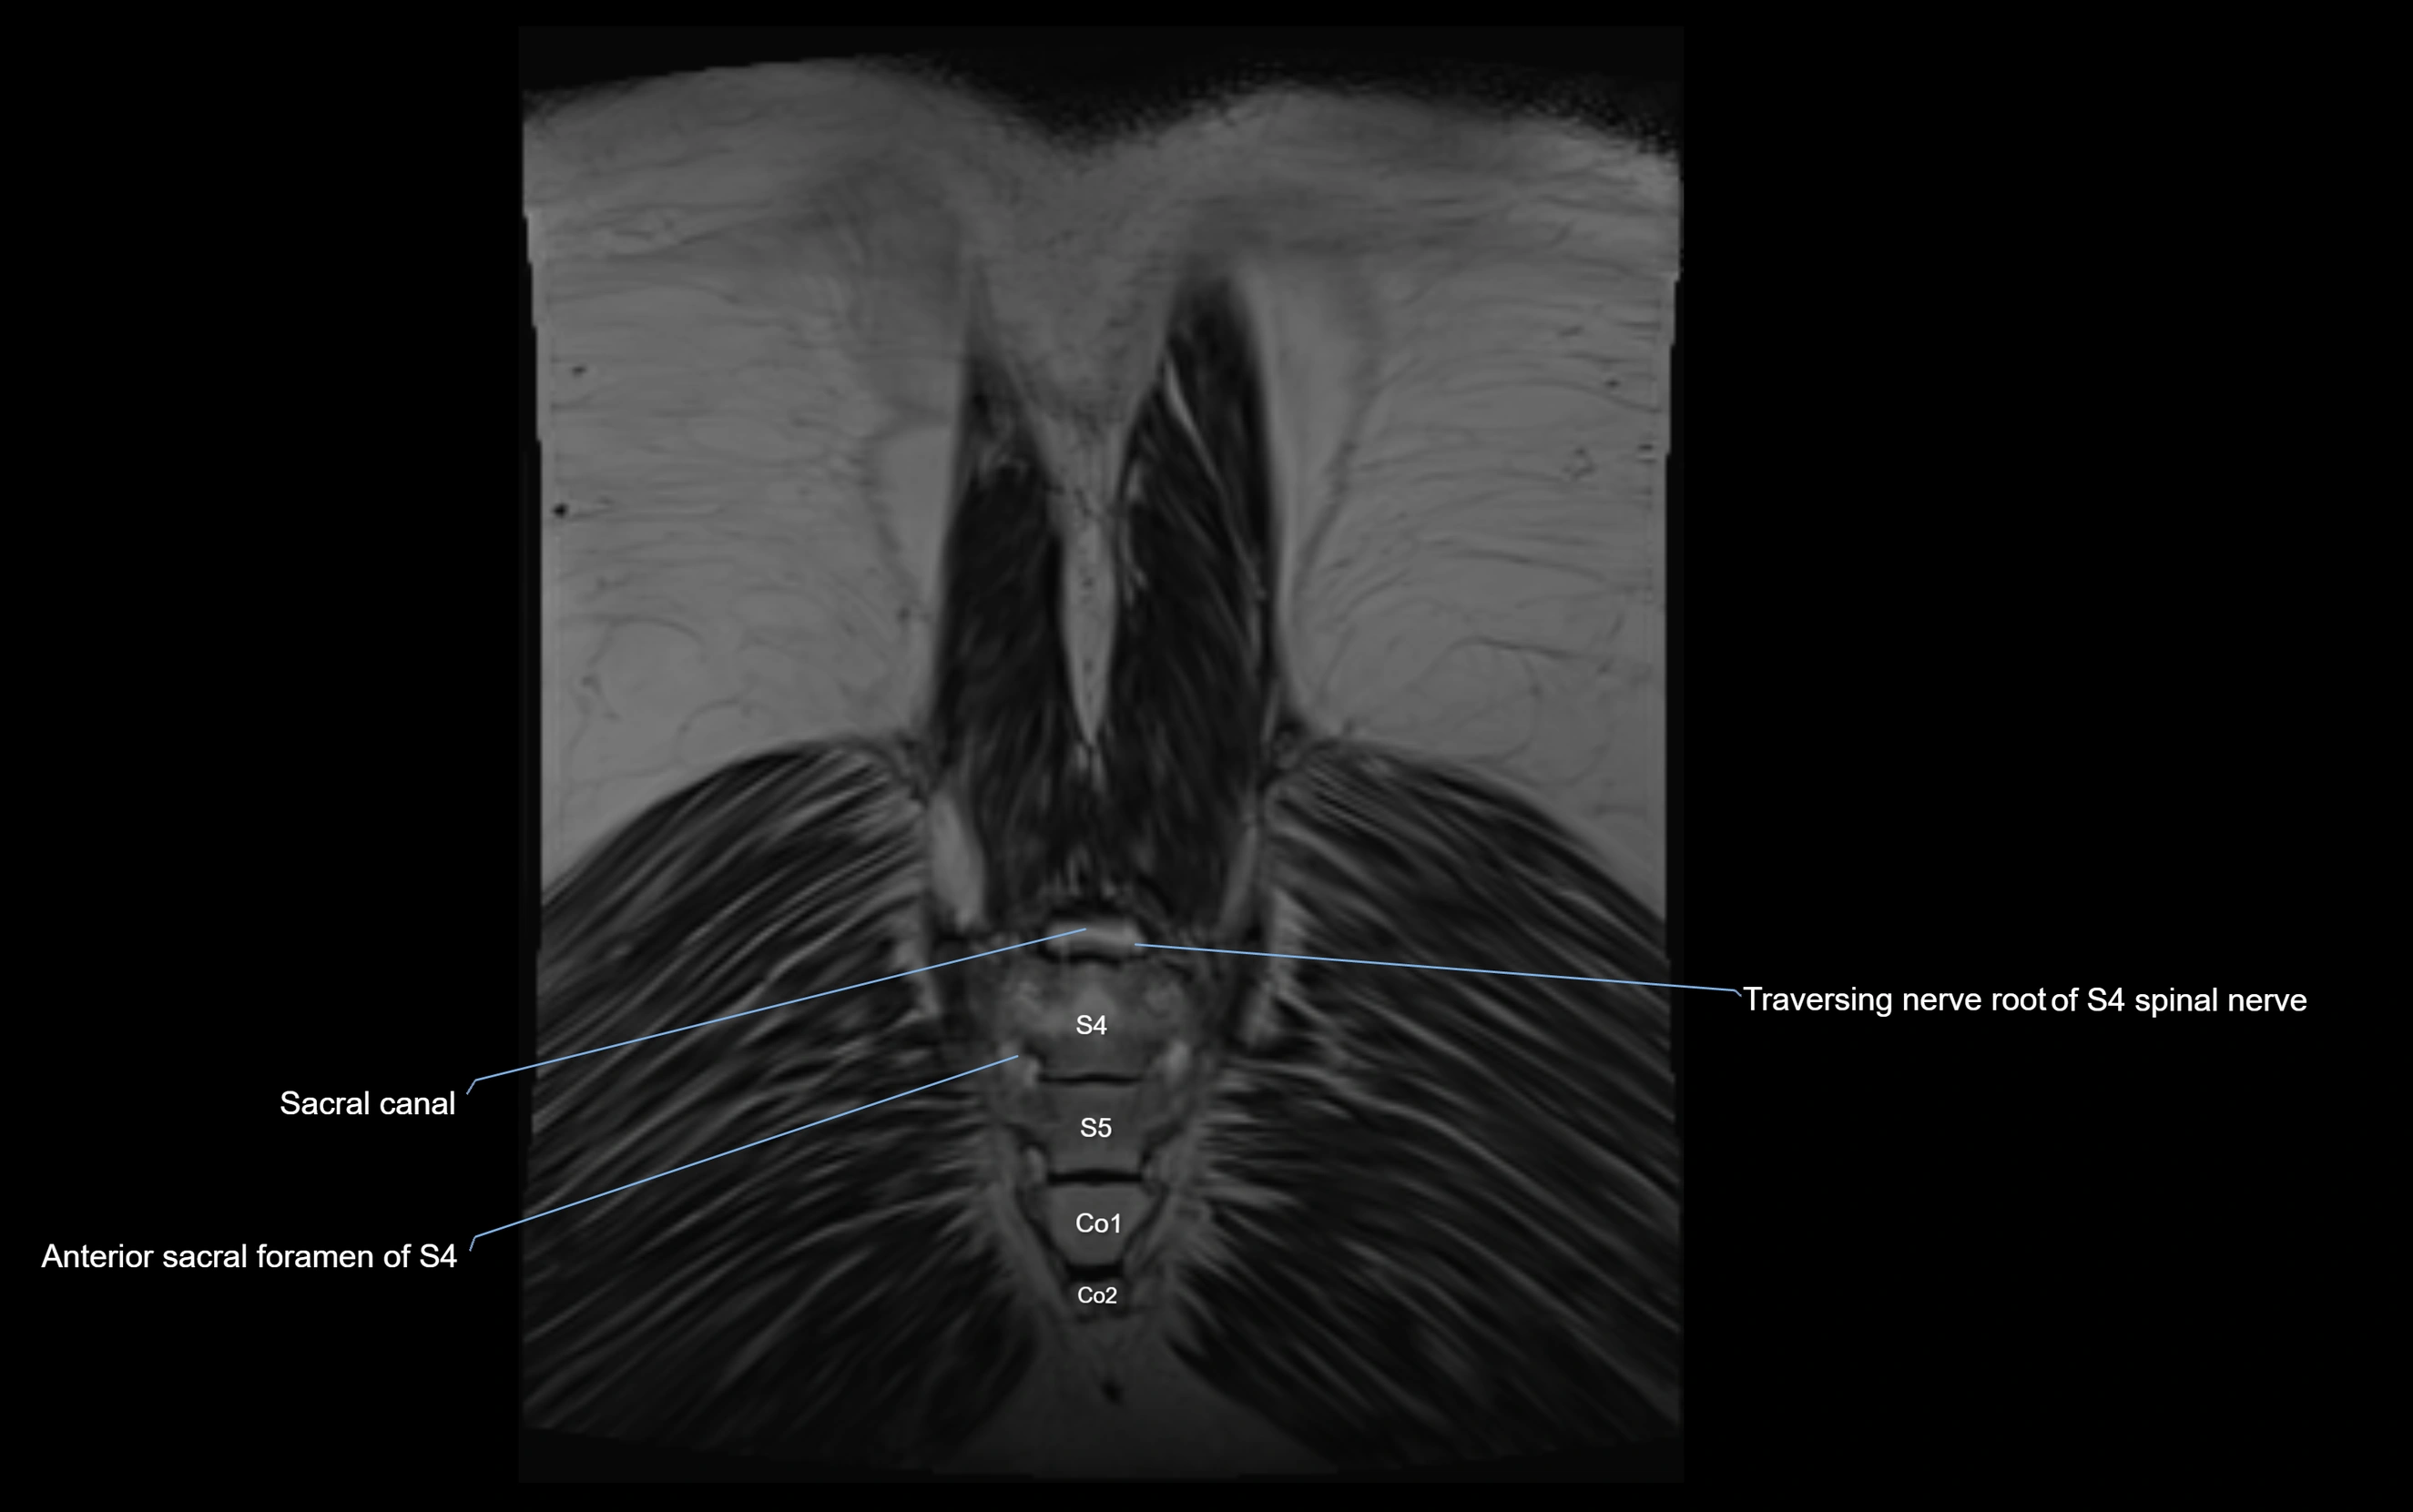

MRI image

image